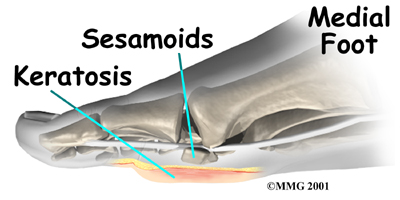

The main joint of the big toe forms the inside edge of the ball of the foot. The two small are located on the underside of this joint. There is of the base of the big toe.

Sometimes sesamoid pain comes from extra tissue under the big toe joint, similar to a corn. Doctors call this extra tissue an intractable .

For patients diagnosed with stubborn plantar keratosis, surgeons generally perform surgery to scrape off the extra tissue. Your surgeon may decide to shave off only the affected part of the bone. The bottom half of the sesamoid is cut off, and the rough edges of the remaining part of the bone are filed with a special tool to leave a smooth shell. This surgery is easier on the body than procedures that completely remove the sesamoid.